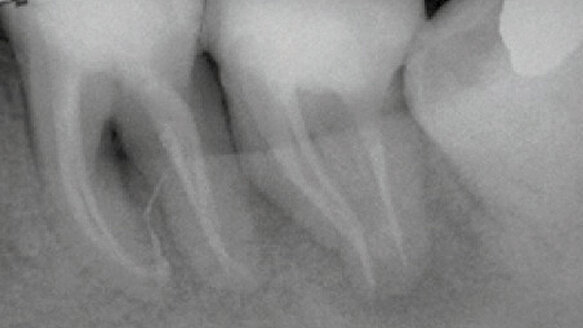

A patient asked for the option to save her teeth that were scheduled for extraction by another dentist. The lower left first and second molars had high mobility (grade 2), were necrotic, with significant probing depths in the buccal aspect. The teeth were diagnosed for endo/perio treatment. Difficulties with this case included complex radicular anatomy, long anatomical measurements (26 and 27 mm respectively for #36 and 37) and the presence of a deep vertical bone loss in the buccal aspect.

No post–op symptoms were reported and the mobility of the teeth progressively disappeared up to grade 0. The follow-up X–rays performed after one and four months showed healing in progress for both the teeth. Lightwalker AT laser device with contact H14–C handpiece and PIPS fiber tip was used for the treatment.